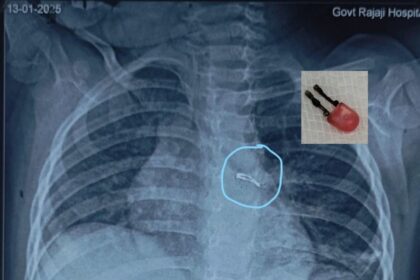

குழந்தையின் மூச்சுக்குழாயில் சிக்கிய ஊக்கு

மதுரை ஜனவரி 18, மதுரை அரசு இராசாசி மருத்துவமனையில் ஒரு வயது குழந்தையின் மூச்சுக்குழாயில் சிக்கிய ஊக்கை…